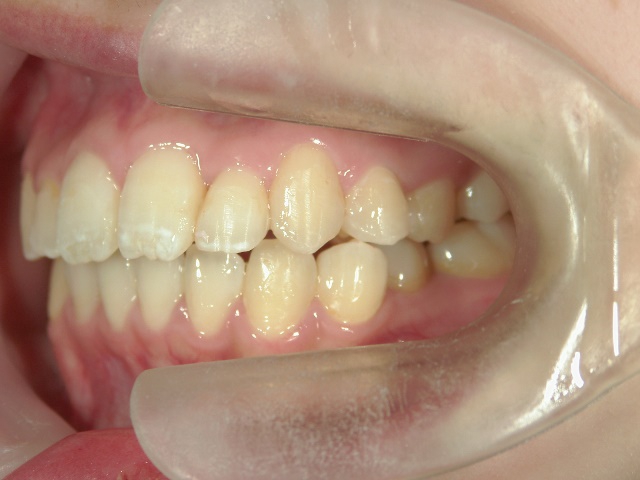

矯正歯科 治療前矯正歯科 治療前

21歳女性 浜松市北区在住

治療期間 8カ月

矯正歯科 治療前

no.8_8495_治療前_左.jpgno.8_8495_治療前_正面.jpgno.8_8495_治療前_右.jpg